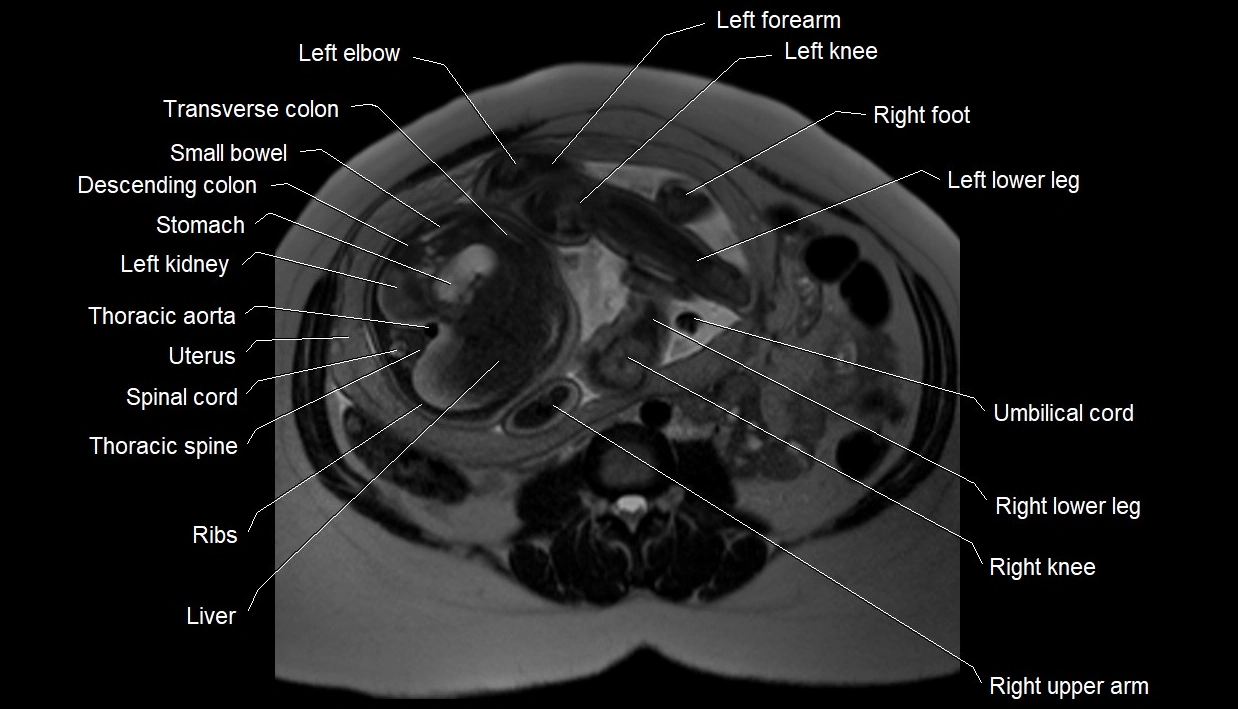

MRI Appearance

T2 HASTE (T2 GRE):

• Amniotic fluid shows very bright hyperintense signal

• Provides natural contrast against fetus and placenta

• Small particles (vernix) may appear as scattered hypointense foci within bright fluid

MRI image

image